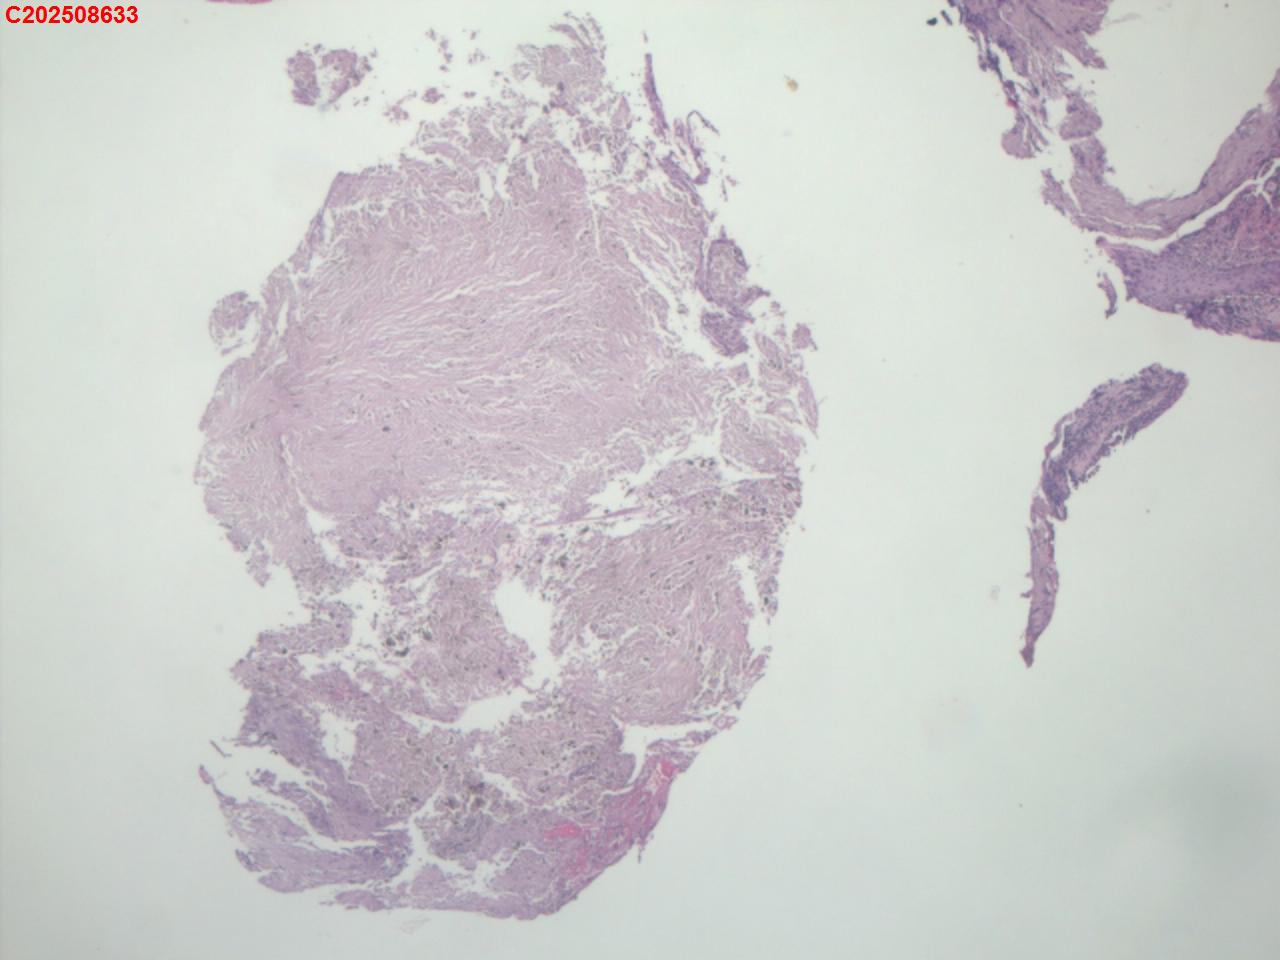

性别年龄82岁临床诊断肺结核?肿瘤?肺部感染?

一般病史2025-07-24 CT检查:考虑右肺上叶炎症伴肺实变,右肺上叶前段支气管显示不明确,建议治疗后复查或支气管镜检查。纵膈多发淋巴结增大。右侧胸腔积液。

标本名称纤支镜咬检

大体所见2025-07-25 气管镜检查示:左侧主支气管、上叶、下叶及各段支气管未见异常。右侧主支气管未见异常。右侧中间段支气管可见碳沫沉积。右肺上叶前段支气管开口可见脓苔附着,支气管开口狭窄,内可见灰黑色新生物阻塞右肺上叶前段支气管管腔。2025-07-25结核感染T细胞检测阳性。2025-07-27肺泡灌洗液查结核分枝杆菌复合群阳性。

坏死物比较多,没有看到明确的肿瘤性病变,可以考虑给一个描述性诊断。